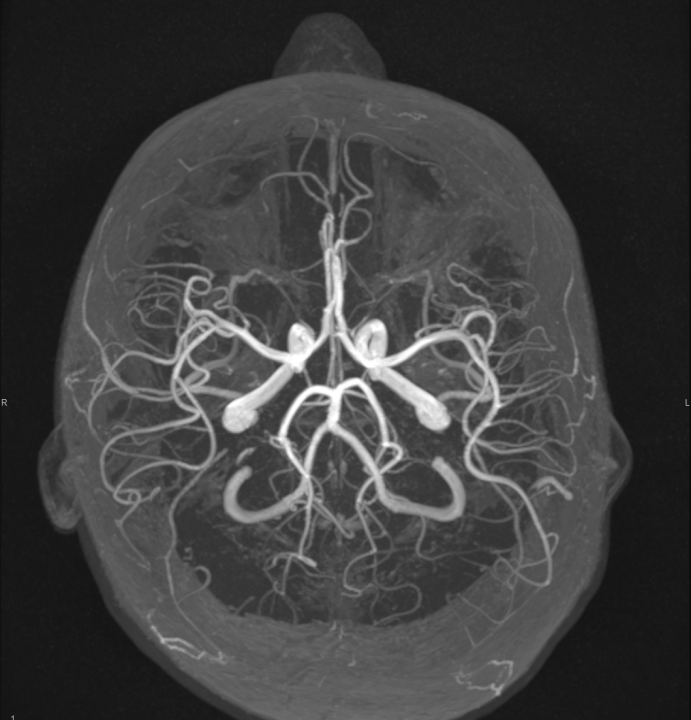

FOTO Ako su vam potrebni specijalistički pregledi mamografija, RTG, UZV, CT i MR, koji se inače koriste za dijagnostiku velikog broja zdravstvenih problema, možete ih obaviti već danas ili sutra. Vodite računa o vašem zdravlju i zakažite pregled u Poliklinici Affidea Vita u Šibeniku na vrijeme!